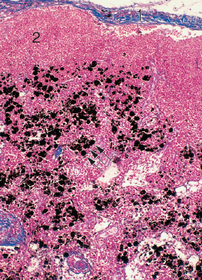

Macrófagos repletos de polvo de carbón

(negros, →) en un ganglio linfático (humano). Los macrófagos aparecen principalmente en la región de la

médula. 1 Cápsula del ganglio linfático; 2 folículo linfático en la corteza.